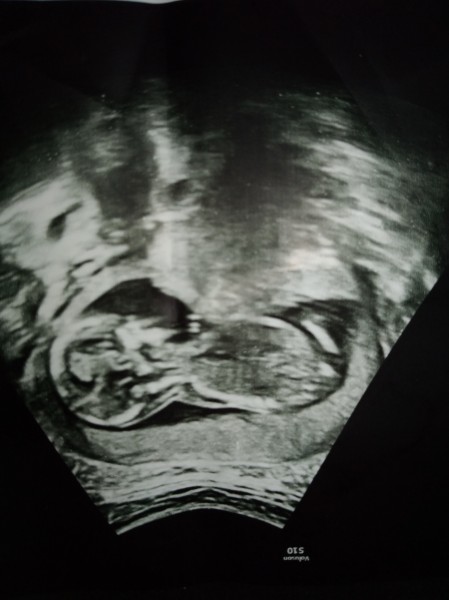

Hamilelik Dönemi Genel kategorisinde (915 puan)

Maksat eğlenmek olsun. Yoksa doktorun bilemedigini biz nasıl bilelim. İcinize bir his doğuyor mu kardeşler

image

? :)

Kapatılma nedeni: Cinsiyet tahminlerini sol üst köşedeki sohbet bölümünde sorabilirsiniz

Bence kıza benziyor

15 ama 16 ile uyumlu. Sizin?

Erkek hiss etdim